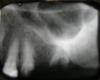

Семь лет назад протезировалась, поставили 2 моста (справа и слева наверху) и сделали бюгель на нижней челюсти (не хватало 5 зубов). На днях возникла проблема с одним из мостов (25-27), он стал немного шататься. С этим вопросом обратилась к своему ортопеду (который все это делал). Он сказал, надо снимать. Снимал не распиливая весь мостик. Как я поняла, у меня изначально проблема была только в 27 зубе - там была большая штифтовая пломба и она отвалилась, а в процессе съема 25 мне просто выломали - отломилась вся короночная часть, остался только корень ниже десны. Корень там вроде прилично запломбирован. Снимок прикрепляю.

1) Можно ли не удалять 25, а его как-то нарастить или коронку поставить на вкладке - как лучше?

2) Можно ли сделать 2 отдельных импланта на 6 и 7 зуб. Мосты ни в каком виде после нынешнего печального опыта не хочется. Да и 8 зуба нет, так что вариант - либо импланты, либо бюгель на 1 крючке и пластине, что вряд ли удобно.

3) Если имланты - то хотелось бы получить совет по материалам и плану лечения (синуслифтинг? какой вариант синуслифтинга? сколько этапов для имплантации?). Интересует самый надежный вариант в плане приживаемости и срока службы. Особенно учитывая состояние носоглотки. Да, и надо ли носоглотку профилактически пролечить? Считаю, что лучше заплатить за более качественный вариант, чем потом мучиться.

я бы удалил 5й зуб и поставил 2 имплантата 5 и 7

надо удалить 5 и 7 зубы, через 4 мес сделать КТ и принять решение о том какой будет синуслифтинг (открытый или закрытый) и в один или 2 этапа.